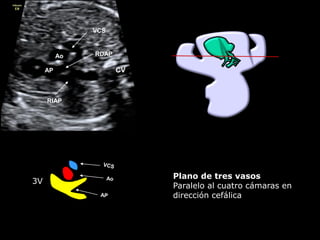

3V

CVAP

Ao

VCS

RDAP

RIAP

Plano de tres vasos

Paralelo al cuatro cámaras en

dirección cefálica

▪ La AP sale del VD

▪ Se dirige hacia la

izquierda y hacia atrás

▪ Se bifurca en ángulo

agudo

▪ Su tamaño es

ligeramente superior al

de la Ao

▪ La VP abre y cierra con

normalidad, dejándose

de visualizar en sístole

▪ Vasos en línea y de

tamaño decreciente

▪ Por doppler color la VP

no presenta

aceleraciones ni reflujos